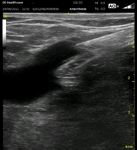

E' consigliata una visita medica specialistica di chirurgia vascolare (o angiologica) sicuramente quando la malattia è conclamata ma anche in presenza di situazioni o condizioni favorenti l'insorgenza di insufficienza venosa degli arti inferiori, anche in assenza di sintomi specifici. La prevenzione della malattia delle vene che si basa principalmente su un adeguato stile di vita, elastocompressione e terapia farmacologica con flebo tonici, va attuata precocemente anche in persone molto giovani, soprattutto se esercitano una professione che obbliga a stare in piedi per molte ore al giorno. L'ecocolordoppler venoso, esame di prima scelta nella diagnostica della malattia delle vene va richiesto sempre dallo specialista vascolare, prima dell'intervento chirurgico e della terapia sclerosante.